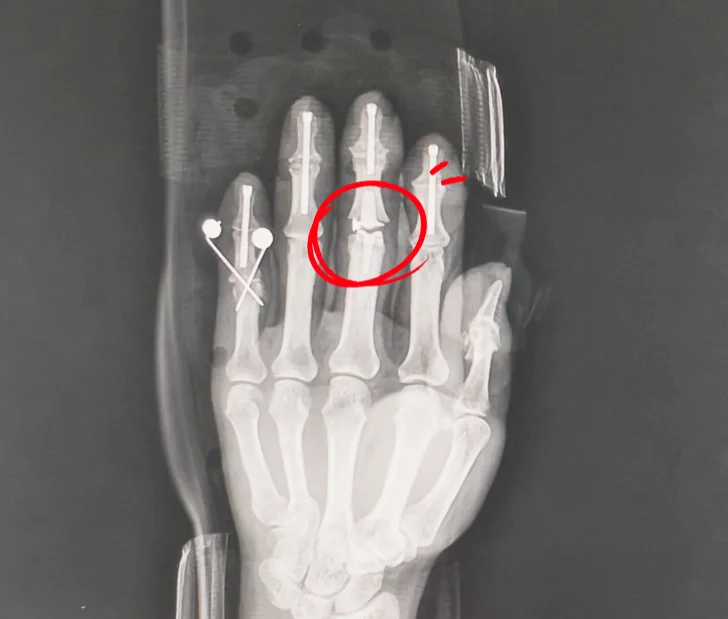

手術を行う前、X-rayを撮って確認したところ

指の関節が完全に壊れていました。

手術法はフュージョン方式と人工関節挿入術で行いました。

フュージョン (fusion)とは、指にネジを入れる手術法を指します。

中指に人工関節が挿入されている様子